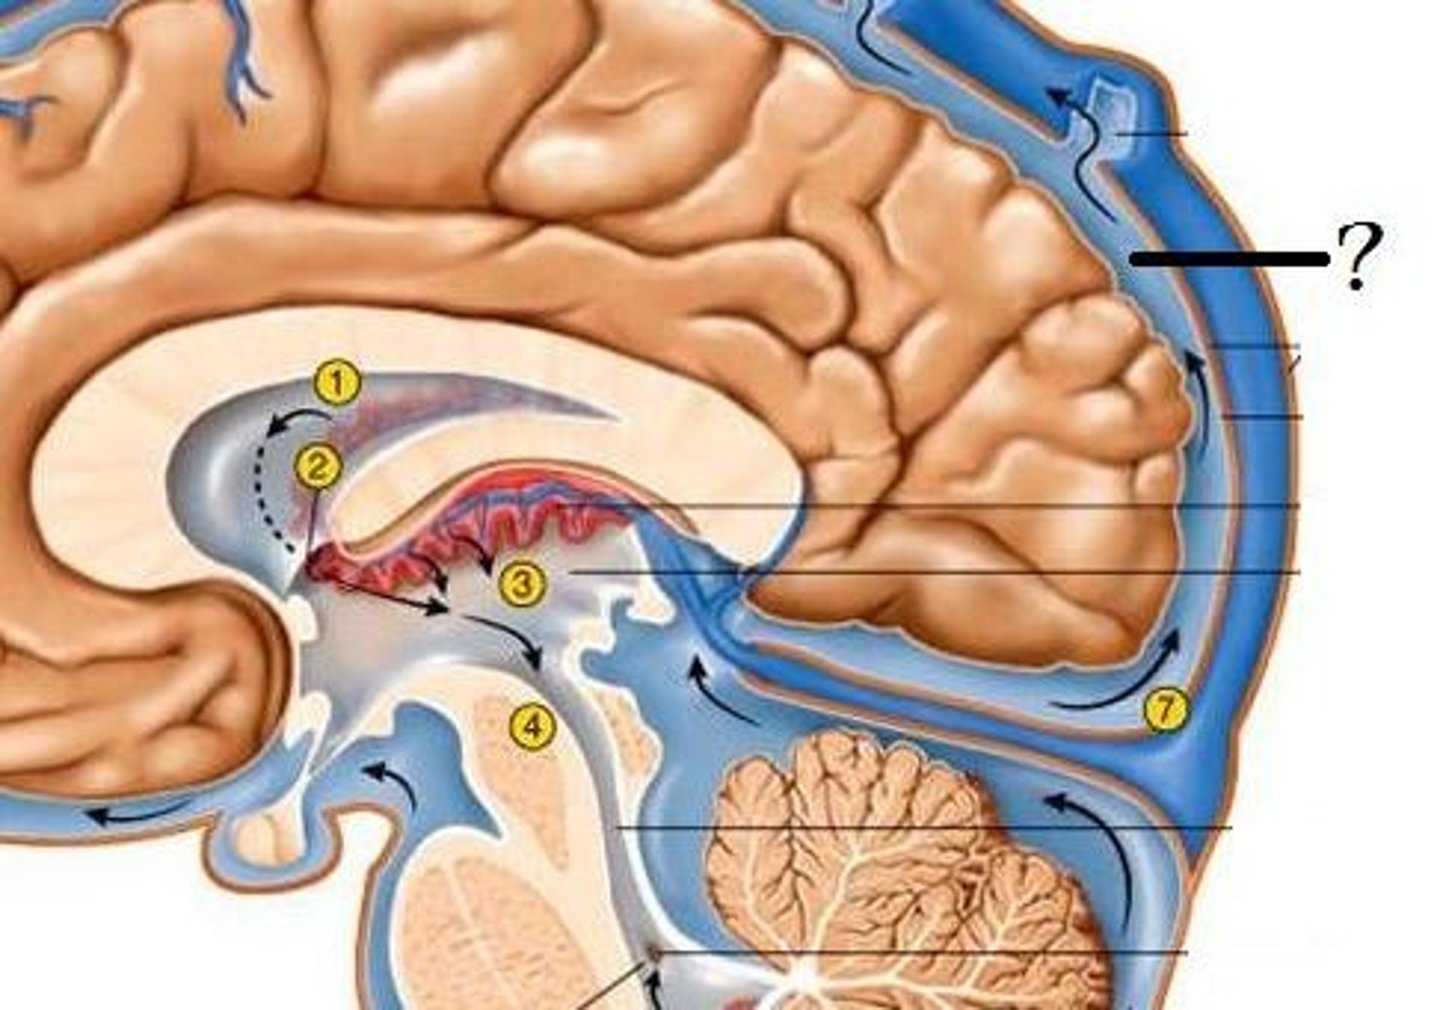

Cerebral Spinal Fluid (CSF)

clear, colourless fluid that circulates within the brain and spinal cord, serving several important functions in the CNS

Circulation of CSF

CSF from the lateral ventricles → interventricular foramina → third ventricle → cerebral aqueduct → fourth ventricle → subarachnoid space or central canal.

mechanical protection of CSF

functions as shock-absorbing medium protecting brain and spina cord

chemical protection in CSF

provides optimal ionic composition for neural signalling

circulation in CSF

helps in exchange of nutrients and waste products between the blood and adjacent nervous tissue

temperature regulation in CSF

helps in maintaining a stable temperature